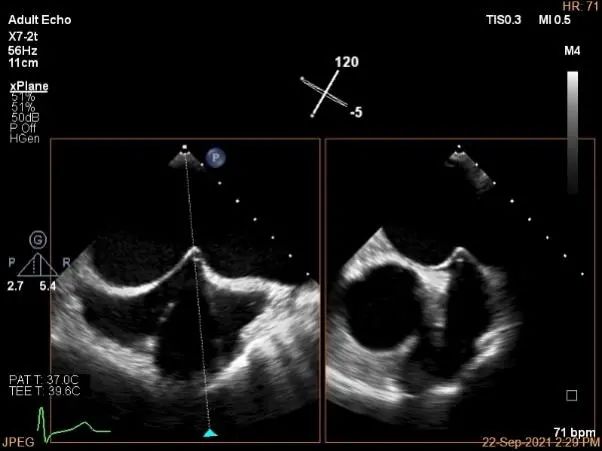

房间隔穿刺点选择

穿刺高度:4.08cm

评估二尖瓣瓣口平均跨瓣压差:1mmHg